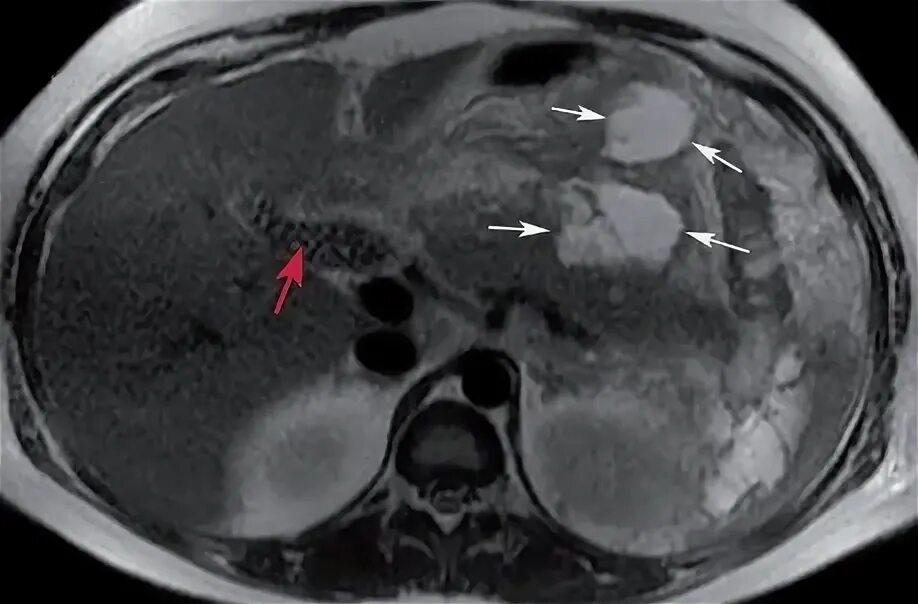

Инфильтрация паранефральной клетчатки на кт. параколитическая клетчатка кт. парапанкреатическая клетчатка инфильтрирована. перипанкреатический инфильтрат.Кт при остром панкреатите. парапанкреатическая клетчатка. кт диагностика панкреатита. острый отечный панкреатит кт.Парапанкреатическая клетчатка. поддиафрагмальное пространство. внебрюшинное поддиафрагмальное пространство. парапанкреатическая клетчатка инфильтрирована.Парапанкреатическая клетчатка что это значитКлетчатка анатомия. понятие о клетчатке в анатомии. основы клинической анатомии. клетчатка понятие.Парапанкреатическая клетчатка что это значитПарапанкреатическая клетчатка. парапанкреатическая клетчатка инфильтрирована. парапанкреатическая инфильтрация. парапанкреатическая клетчатка дифференцирована.Парапанкреатическая клетчатка что это значитПарапанкреатическая клетчатка что это значитХронический панкреатит на кт. парапанкреатическая клетчатка на кт. кт поджелудочной железы. поджелудочная железа на рентгенограмме.Парапанкреатическая клетчатка что это значитПарапанкреатическая клетчатка что это значитПарапанкреатический инфильтрат. парапанкреатическая клетчатка дифференцирована.Парапанкреатическая клетчатка что это значитПарапанкреатическая клетчатка что это значитПарапанкреатическая клетчатка поджелудочной железы. отек парапанкреатической клетчатки. парапанкреатическая инфильтрация. острый деструктивный панкреатит кт.Парапанкреатическая клетчатка что это значитПарапанкреатическая клетчатка что это значитПарапанкреатическая клетчатка что это значитПарапанкреатическая клетчатка что это значитПарапанкреатическая клетчатка что это значитПарапанкреатический инфильтрат. перипанкреатический инфильтрат. парапанкреатическая псевдокиста на кт.Парапанкреатическая клетчатка что это значитПарапанкреатическая клетчатка что это значитПарапанкреатическая клетчатка что это значитПарапанкреатическая клетчатка что это значитПарапанкреатическая клетчатка что это значитПарапанкреатическая клетчатка что это значитПарапанкреатическая клетчатка что это значитПарапанкреатическая клетчатка что это значитПарапанкреатическая клетчатка что это значитПарапанкреатическая клетчатка поджелудочной железы. перипанкреатический инфильтрат. осложнения острого панкреатита презентация. перипанкреатическая клетчатка.Парапанкреатическая клетчатка что это значитКисты и свищи поджелудочной железы. инфильтрация парапанкреатической клетчатки. истинные кисты поджелудочной железы классификация. парапанкреатическая клетчатка поджелудочной железы.Парапанкреатическая клетчатка что это значитПарапанкреатическая клетчатка что это значитПарапанкреатическая клетчатка что это значитПарапанкреатическая клетчатка что это значитПарапанкреатическая клетчатка что это значитПарапанкреатическая клетчатка что это значит